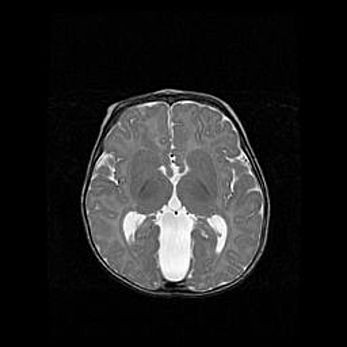

Множественные кисты обоих полушарий головного мозга, наибольшая из них в правой затылочной области. Ассиметричная атрофическая гидроцефалия.

Возраст: 7 месяцев

Вес: 5660 г

Пол: мужской

Окружность головы: 41,5 см

Срок гестации: 28-29 недель

Кисты головного мозга развиваются в результате многоочаговых некрозов вещества мозга и возникают вследствие перенесенной перинатальной инфекции, менингитов, энцефалитов, асфиксии, родовой травмы, расстройств мозгового кровообращения различного генеза. Образованию кист в веществе головного мозга плодов и новорожденных способствуют такие факторы, как высокое содержание в нем воды, недостаточная (или отсутствие) миелинизация и слабая астроглиальная реакция на повреждение.

Кисты могут сочетаться с гидроцефалией и другими поражениями головного мозга.